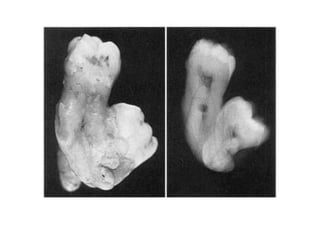

8. Gemination

Merupakan anomali yang terjadi ketika satu

tooth bud berusaha untuk membelah.

6. Fusion

Merupakan hasil dari penggabungan dua

benih gigi bersebelahan yang sedang

berkembang.